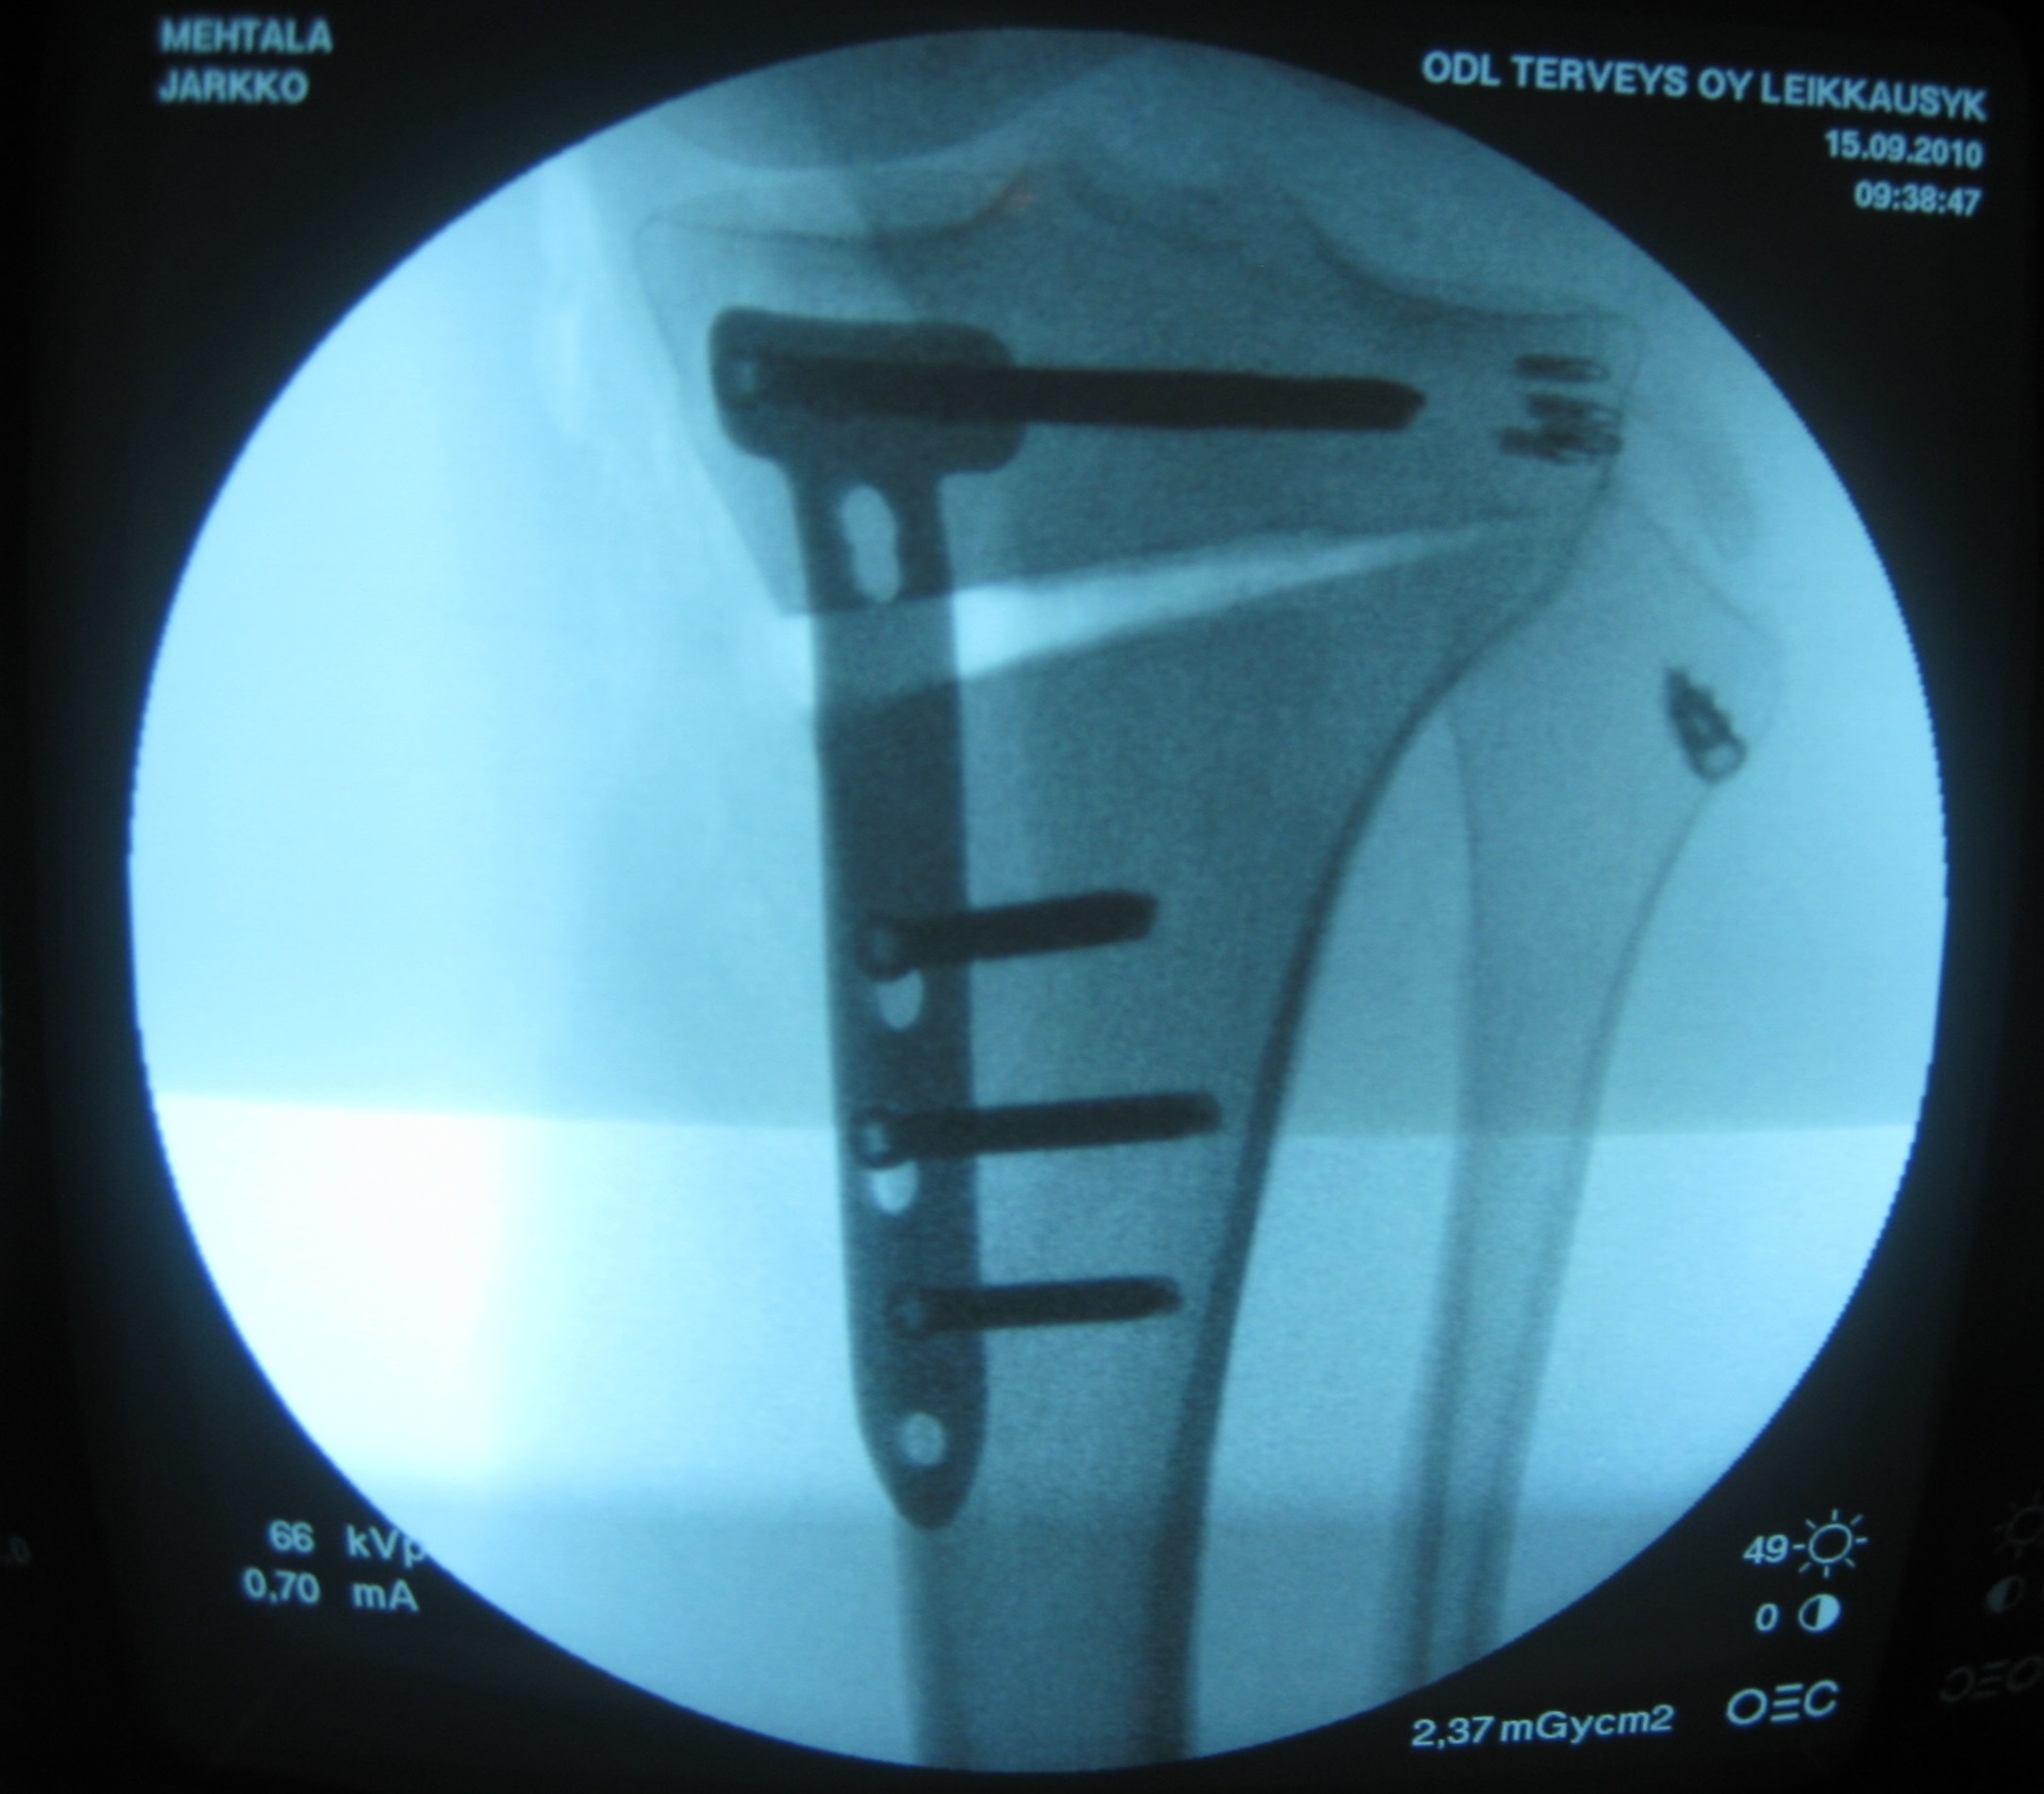

Jarkko Mehtälän vasemmasta polvesta on aikoinaan rikkoutunut etu- ja takaristiside sekä ulompi sivuside. Tämän lisäksi on ollut useita pienempiä loukkaantumisia. Leikkauksia on takana kolme kappaletta. Lisäksi Mehtälän keskisormi on litistynyt, jolloin siitä halkesi luu.

Röntgenkuvassa näkyvät polvivamman raudoitukset.